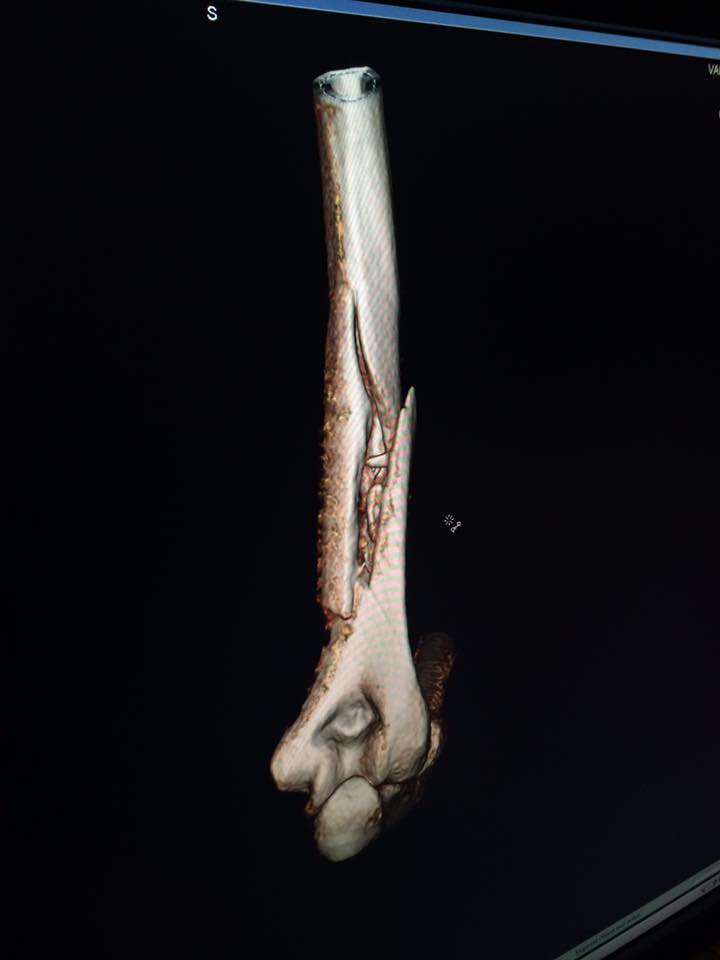

Ad annunciare la caduta e lo stop a causa della rottura del braccio è la stessa campionessa Usa, che su Facebook ha pubblicato uno status corredato con le radiografie che mostrano le fratture sul suo braccio:

“Sfortunatamente, ieri sono caduta mentre mi stavo allenando a Copper e ho riportato una grave frattura dell’osso omero del mio braccio destro. Sono stata operata la scorsa notte a Vail con successo e tutti si sono presi cura di me alla grande.